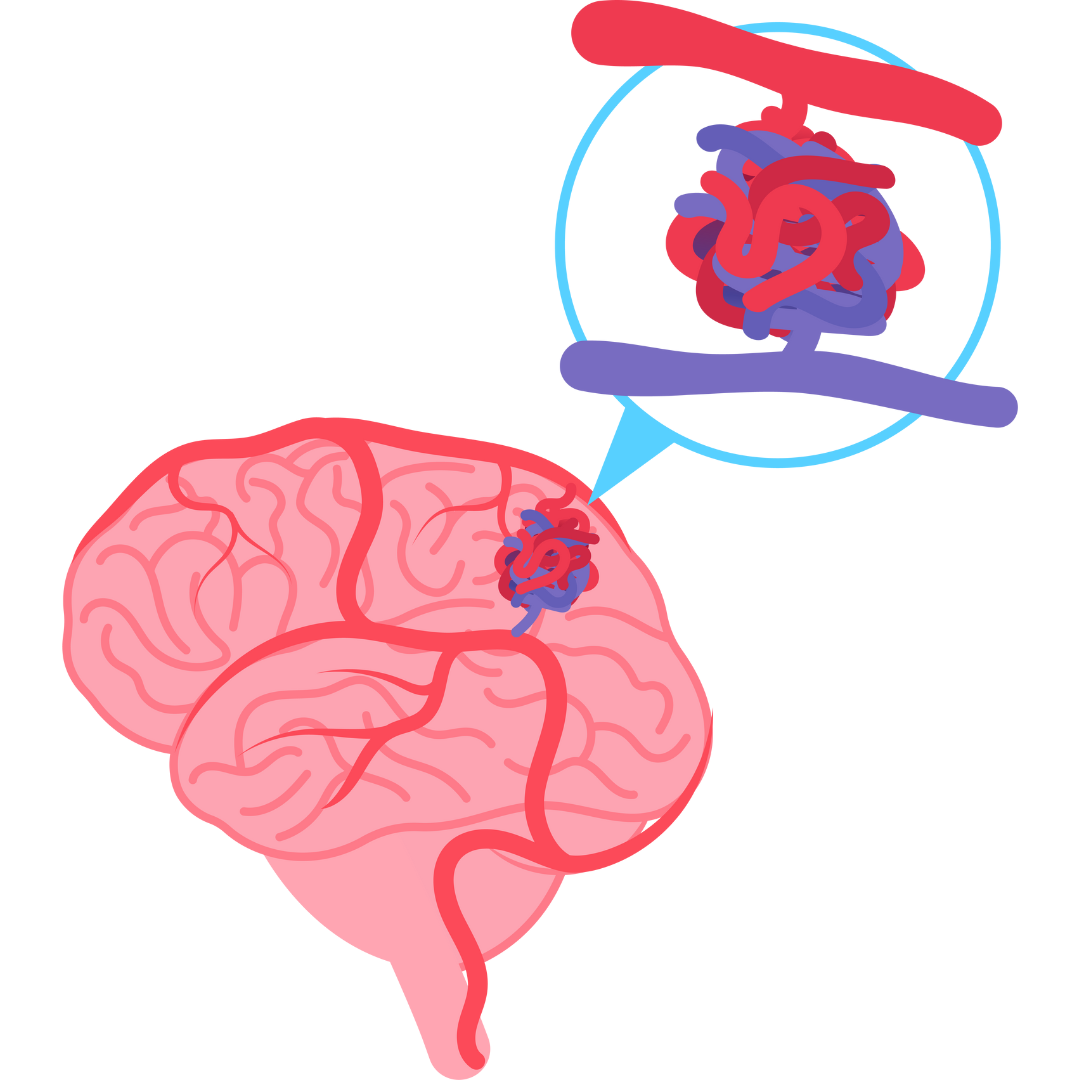

Aneurysm

Our neurosurgeon offers expert care for aneurysms, providing comprehensive evaluations and treatments to reduce the risk of rupture and promote neurological health.

Neuro Vascular Surgery (AVM)

Our neurosurgeon specializes in neurovascular surgery, offering advanced interventions to treat vascular disorders, optimize blood flow, and improve overall neurological health.